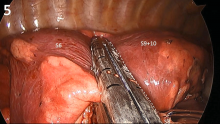

Uniportal VATS Left Posterobasal Anatomical Segmentectomy (S9+10) [1]

This video shows a posterobasal (S9+10) left lower lobe segmentectomy for a lepidic adenocarcinoma of 1.7 cm without nodal involvement. Arterial segmental division can be easily achieved when the pulmonary artery is divided by identifying the central branch of the artery (between the upper segment artery A6 and the anterior segment artery A8). Division of the vein requires careful identification of segmental veins for the upper segment, anterior segment, and posterobasal segments. There is a high frequency of variation in the intersegmental veins, so special attention should be focused to clearly determine which of the veins drains S9+10 in order to preserve venous drainage for the remaining segments and avoid segmental infarction [4].

What the authors find most difficult in this procedure is division of the bronchus and the intersegmental fissures. The segmental bronchus for S9+10 lies just below the arterial stump for the segments, but dissection and division is difficult due to its central location within the lobe. After dissection of the S9+10 bronchus, the authors prefer to first divide the anterior intersegmental fissure (between S8 and S9+10) with endostaplers. After that, they divide the superior intersegmental fissure between the upper segment (S6) and the anterior segment (S8). For this, they place the anvil of the stapler above the pulmonary artery and the segmental bronchus, and pull the parenchyma between those segments (S6 and S8 initially, S6 and S9+10 in the posterior portion) towards the stapler. After this maneuver, segmental bronchial division with a stapler can be easily performed. Finally, it is only necessary to divide the intersegmental fissures, being careful with the segmental veins for the remaining segments in order to preserve them.